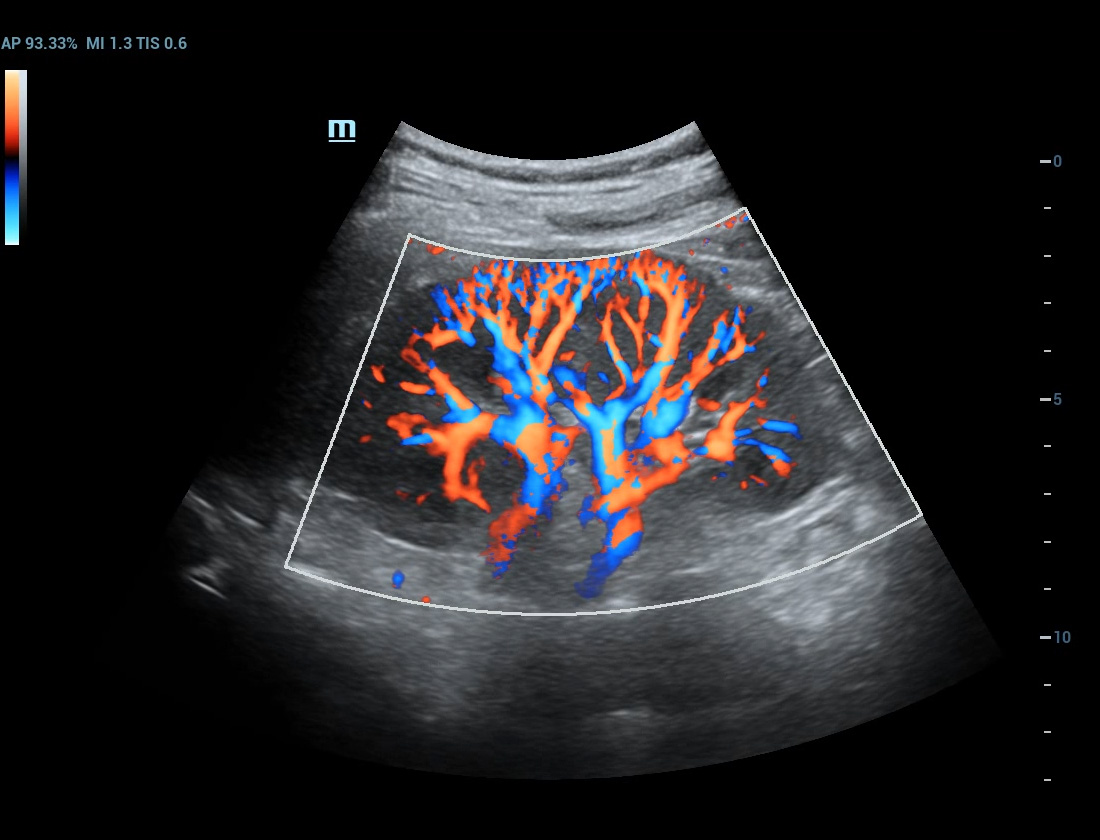

Angiografia ultramicroscû°pica (Ultra Micro Angiography, UMA)

UMA aumenta a confian?a diagnû°stica ao expandir a visibilidade dos fluxos sanguûÙneos atûˋ o nûÙvel de vasos minû¤sculos, com sensibilidade e resolu??o superiores.

sUMA ã Rins

pUMA ã Massa mamûÀria

sUMA ã C?ncer de tireoide

cUMA ã Massa mamûÀria

Massa mamûÀria

pUMA ã Rim